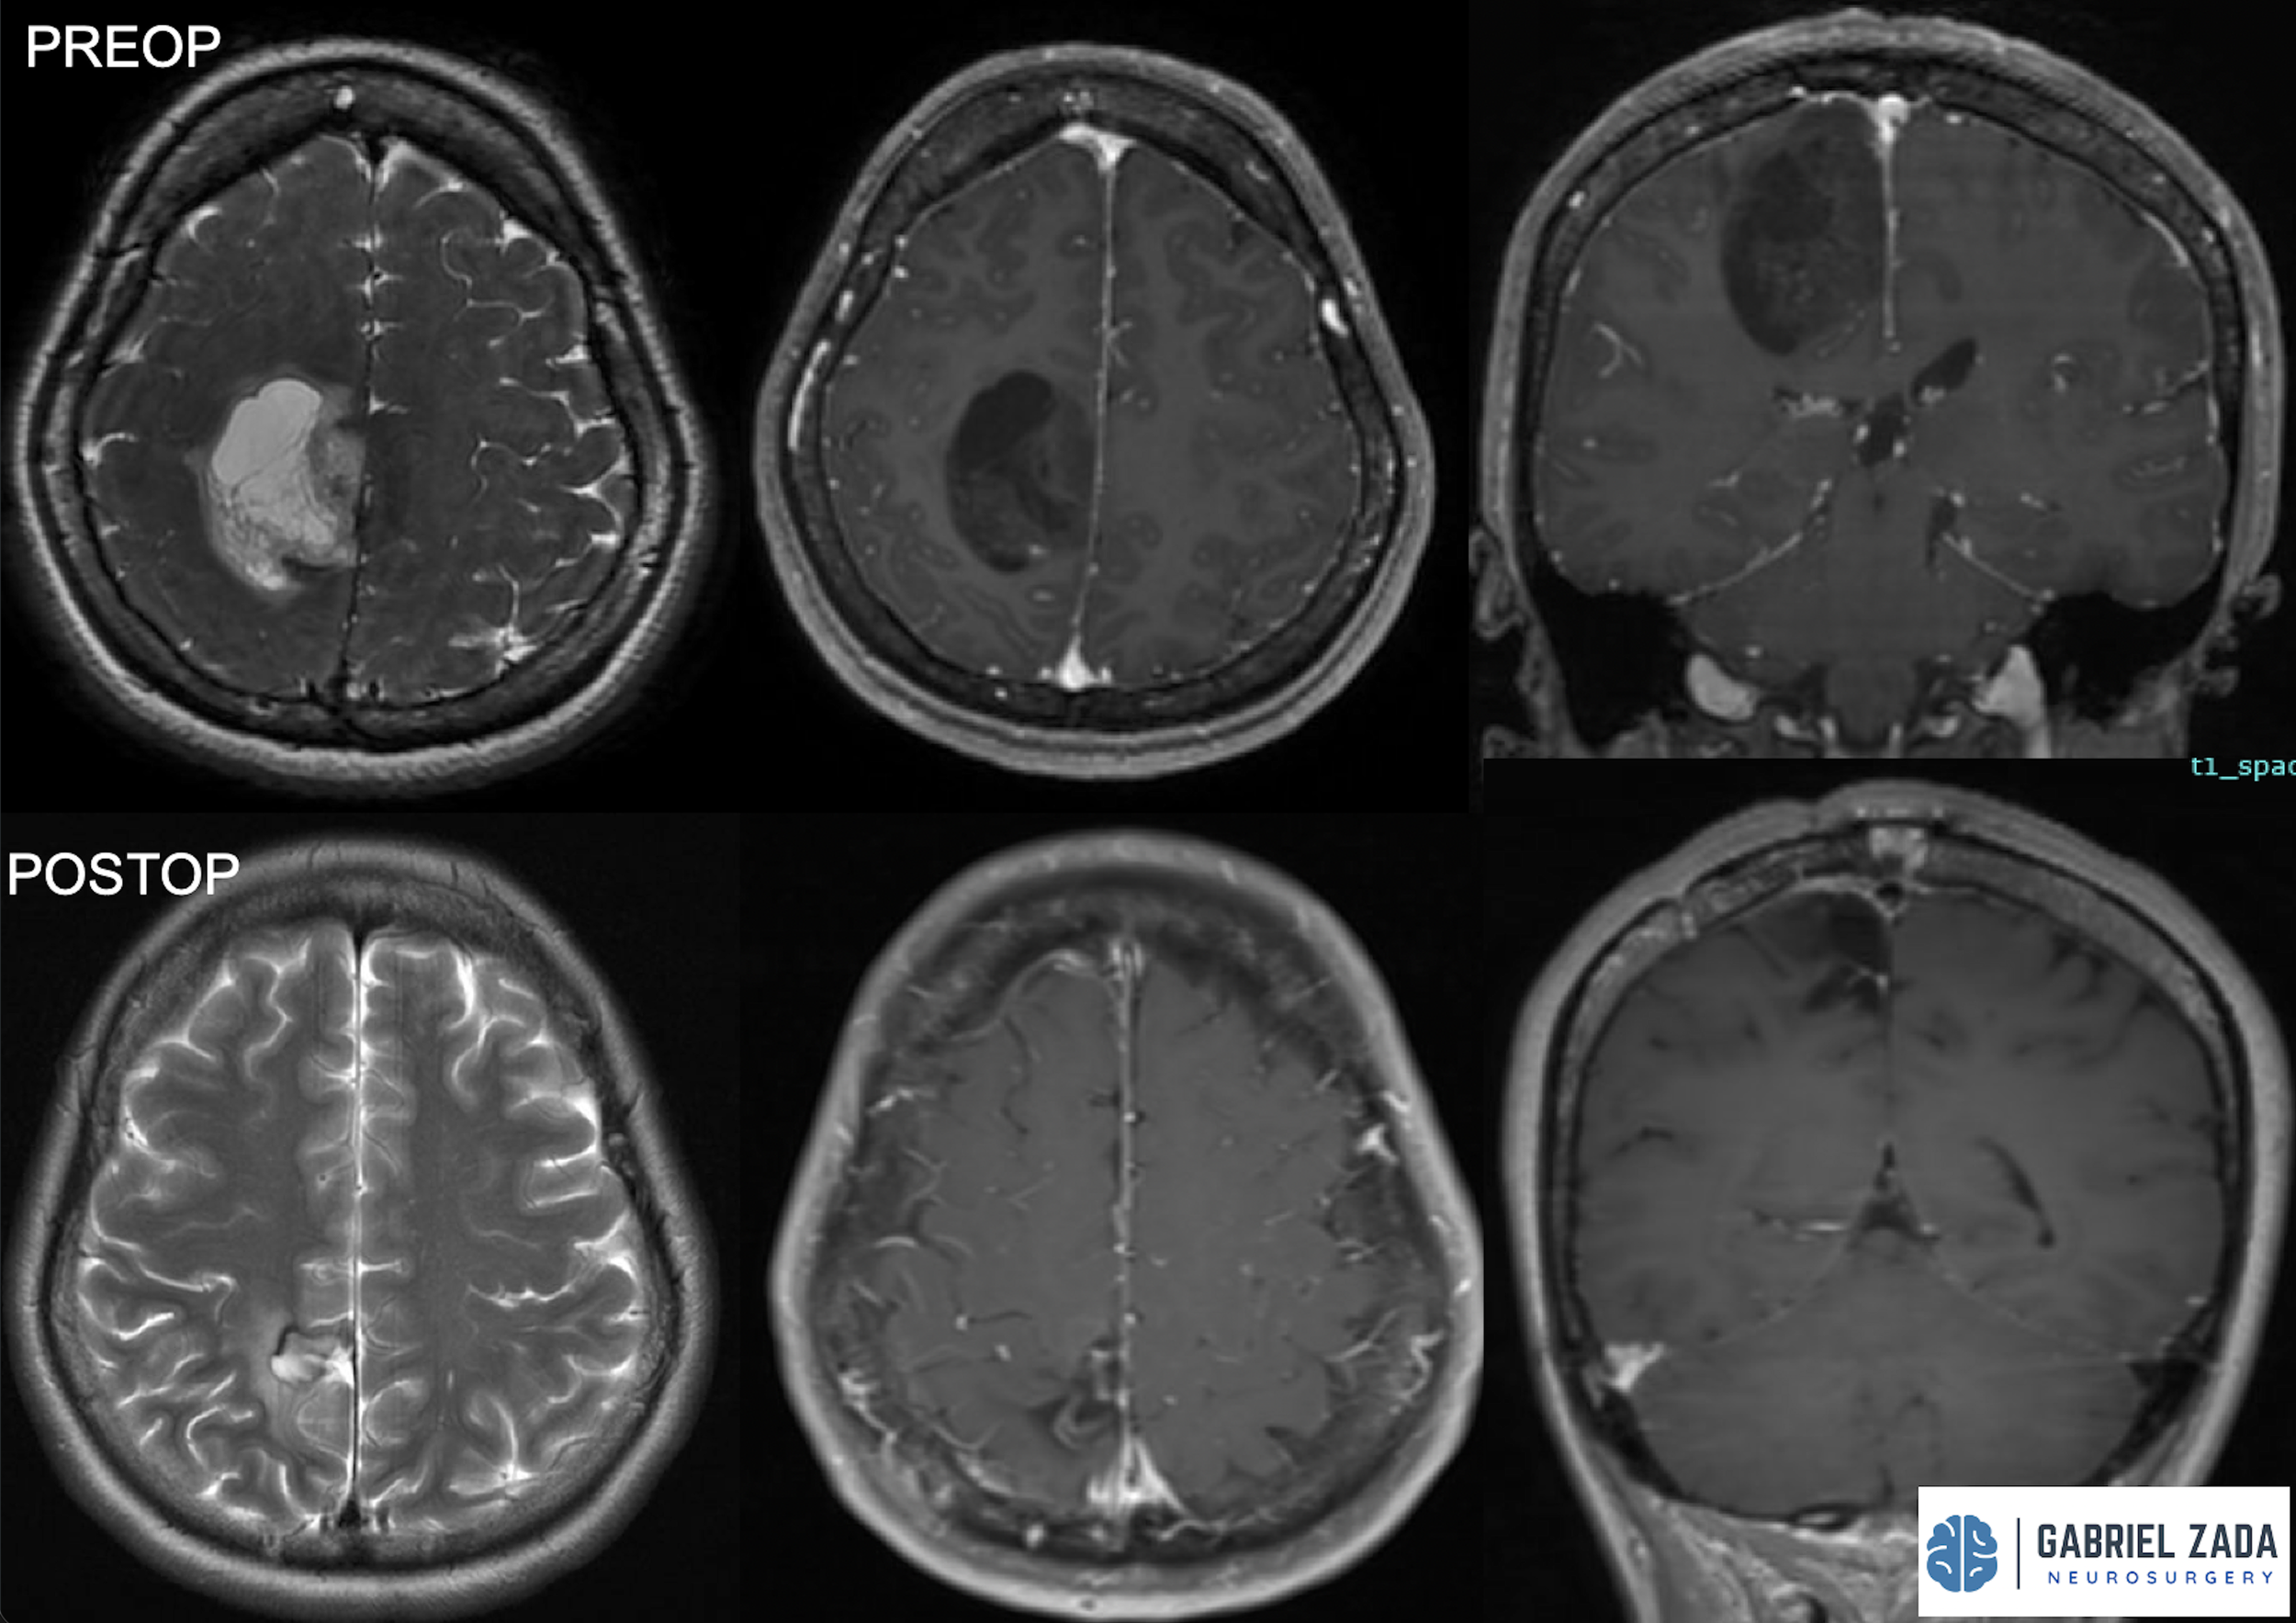

Explore this comprehensive gallery featuring pre‑ and post‑operative imaging of patients with skull‑base tumors treated by Gabriel Zada, MD, MS, FAANS, FACS. These cases highlight Dr. Zada’s expertise in advanced neurosurgical techniques and outcomes.

*Representative cases shown for educational purposes. All images de-identified. Individual results vary.